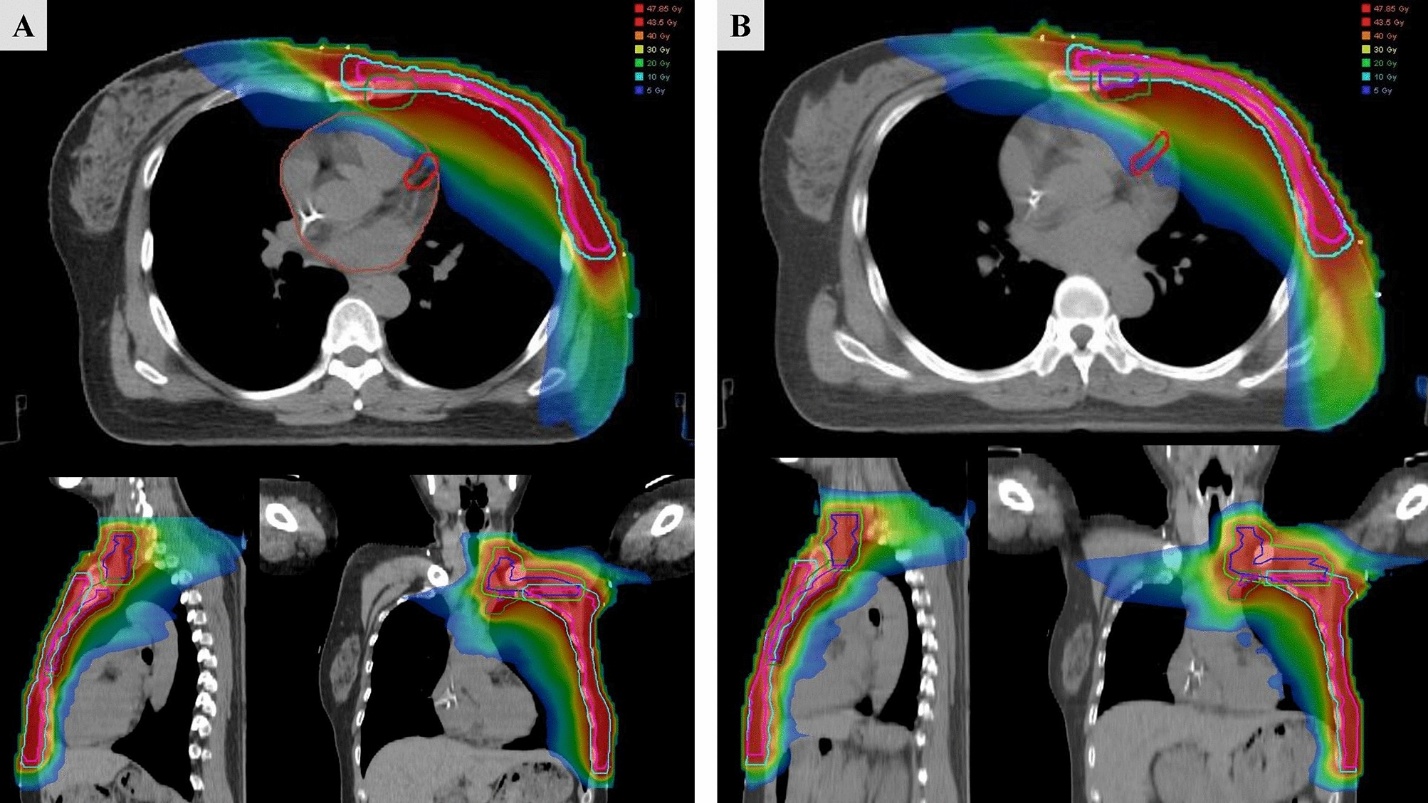

Phân bố liều trong (A) DIBH (Deep Inspiration Breath-Hold – hít sâu nín thở) và (B) FB (Free Breathing – thở tự do) theo kỹ thuật VMAT ở một người bệnh điển hình được chiếu xạ hạch vú trong. Các đường viền màu biểu thị CTV (thể tích bia lâm sàng) và PTV (thể tích bia lập kế hoạch) của vùng thượng đòn/hạ đòn, thành ngực và chuỗi hạch vú trong.

Phân bố liều trong (A) DIBH (Deep Inspiration Breath-Hold – hít sâu nín thở) và (B) FB (Free Breathing – thở tự do) theo kỹ thuật VMAT ở một người bệnh điển hình được chiếu xạ hạch vú trong. Các đường viền màu biểu thị CTV

(thể tích bia lâm sàng) và PTV (thể tích bia lập kế hoạch) của vùng thượng đòn/hạ đòn, thành ngực và chuỗi hạch vú trong.